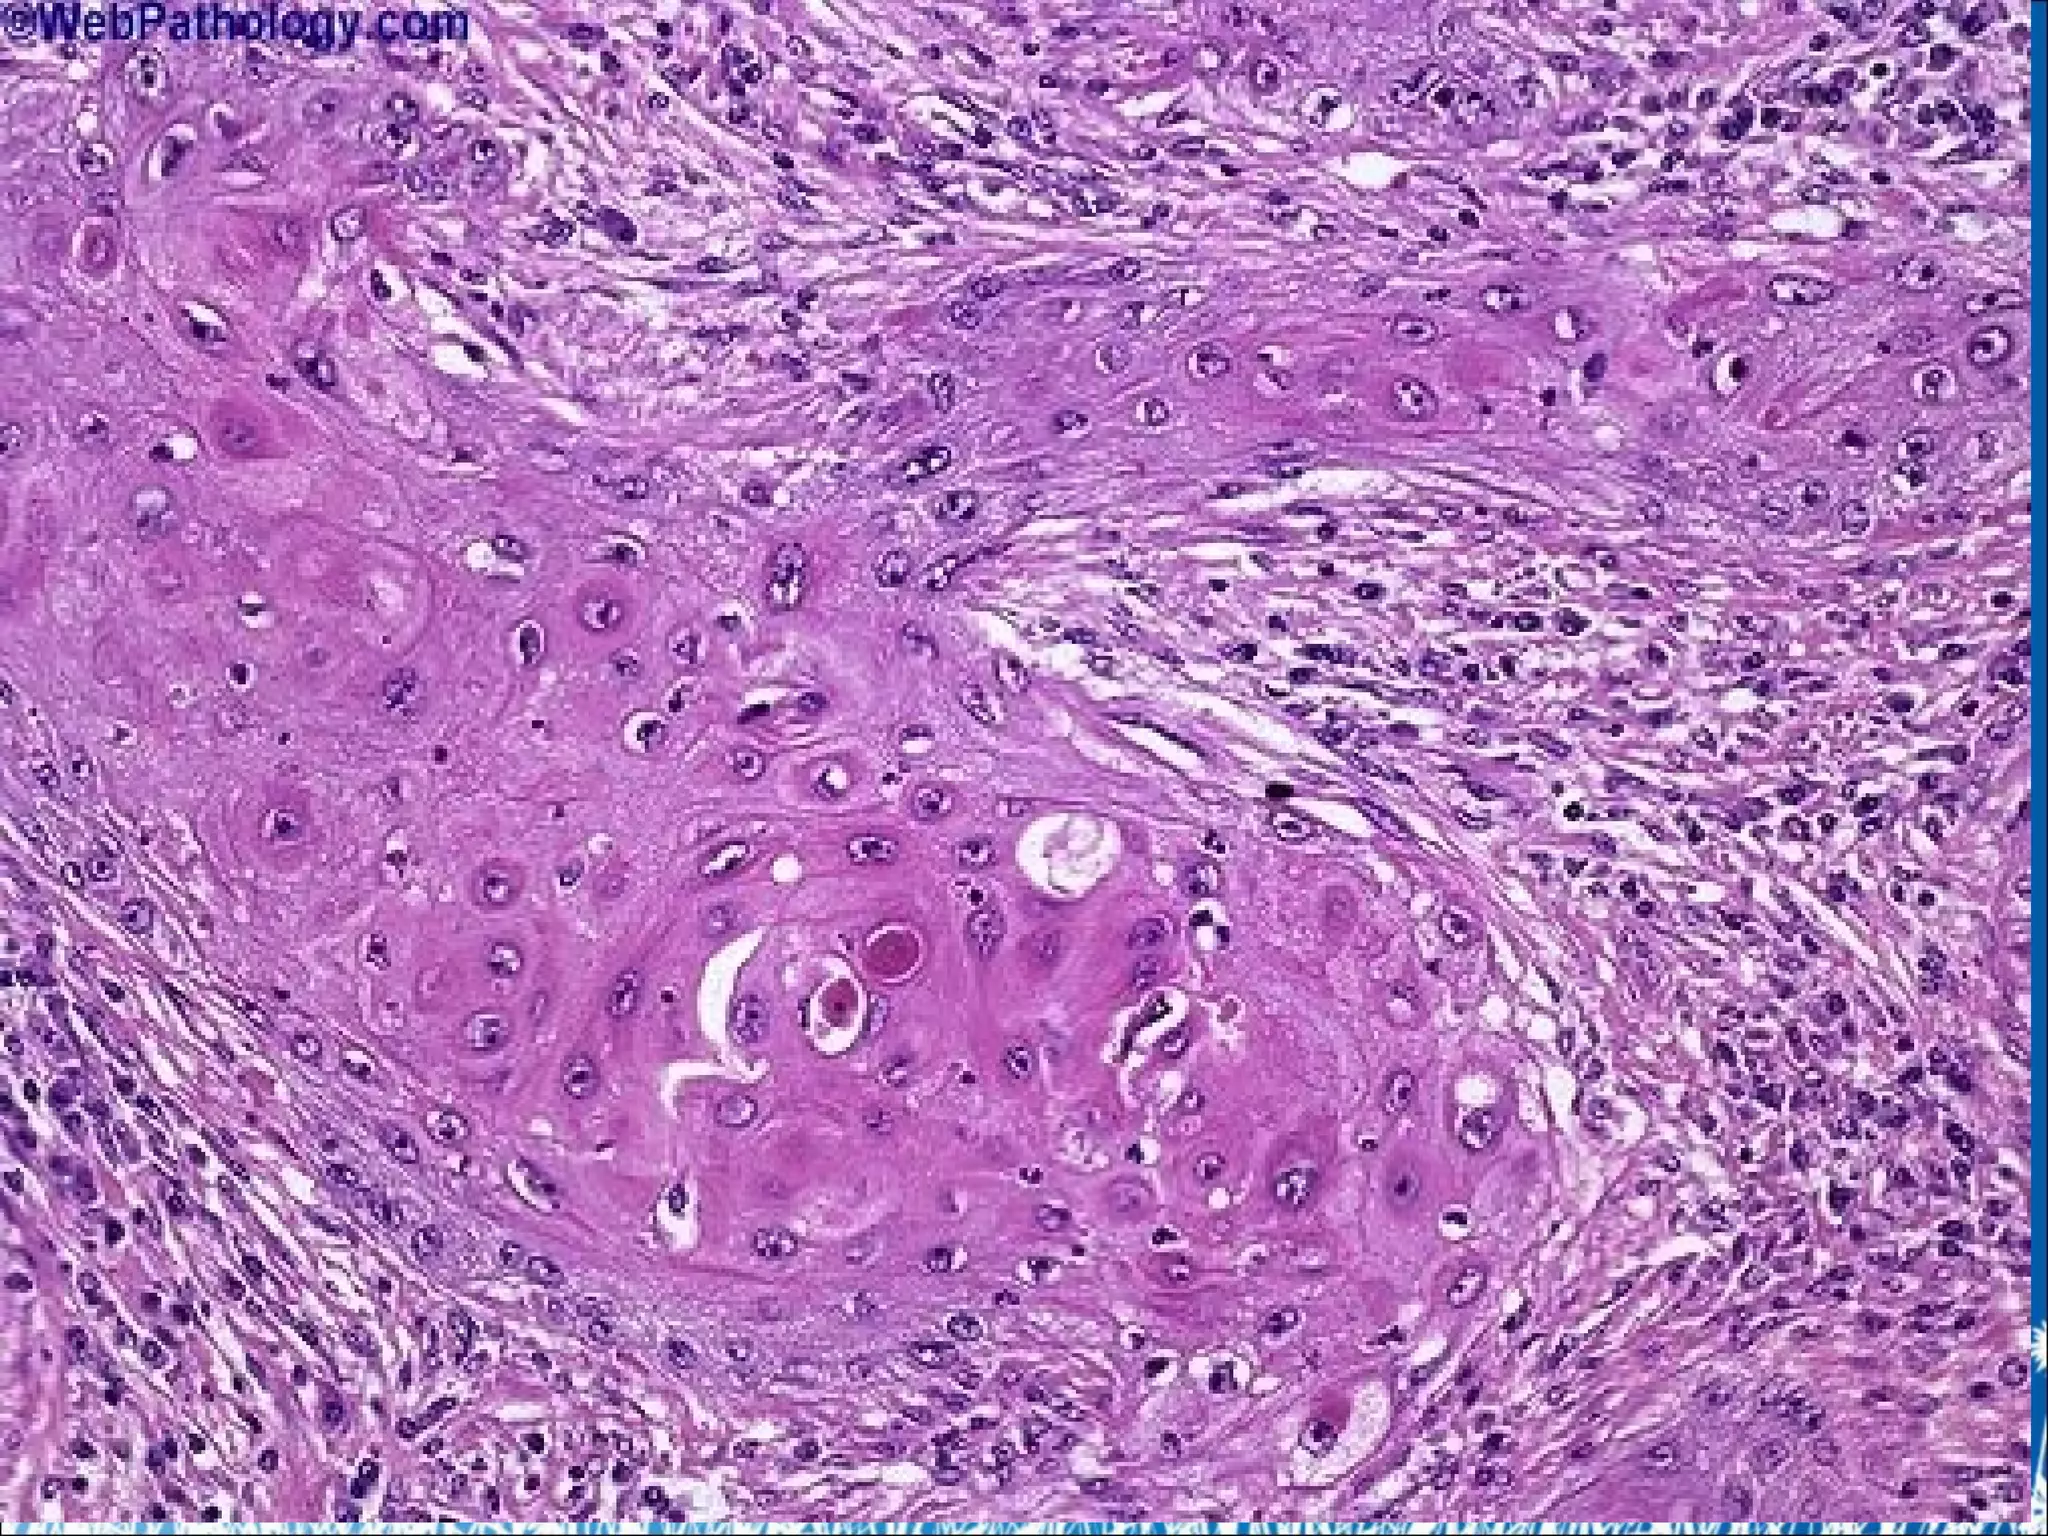

4. Ung thư biểu mô biểu bì tế bào vảy

(Carcinoma tế bào vảy của da)

• ĐN: U ác tính phát sinh từ lớp đáy của biểu mô biểu bì, tế

bào u biệt hoá gợi hình đa diện, xếp thành đám lớn nhỏ

phá vỡ cấu trúc thượng bì xâm nhập sâu xuống trung bì ...

 Tế bào u: Hình đa diện, to nhỏ không đều, bào tương

rộng, sáng hoặc ưa toan, nhiều nhân chia.

 Mô u: Đám/ đảo lớn nhỏ xuất hiện ở trung bì.

 Trung tâm mô u có thể có “cầu sừng” (do các tế bào u

chết đi sừng hóa thành)

 Mô đệm: Xâm nhập viêm lympho, mạch máu sung huyết

4. Ung thưbiểu mô biểu bì tế bào vảy (Carcinoma tế bào vảy của da) • ĐN: U ác tính phát sinh từ lớp đáy của biểu mô biểu bì, tế bào u biệt hoá gợi hình đa diện, xếp thành đám lớn nhỏ phá vỡ cấu trúc thượng bì xâm nhập sâu xuống trung bì ...  Tế bào u: Hình đa diện, to nhỏ không đều, bào tương rộng, sáng hoặc ưa toan, nhiều nhân chia.  Mô u: Đám/ đảo lớn nhỏ xuất hiện ở trung bì.  Trung tâm mô u có thể có “cầu sừng” (do các tế bào u chết đi sừng hóa thành)  Mô đệm: Xâm nhập viêm lympho, mạch máu sung huyết